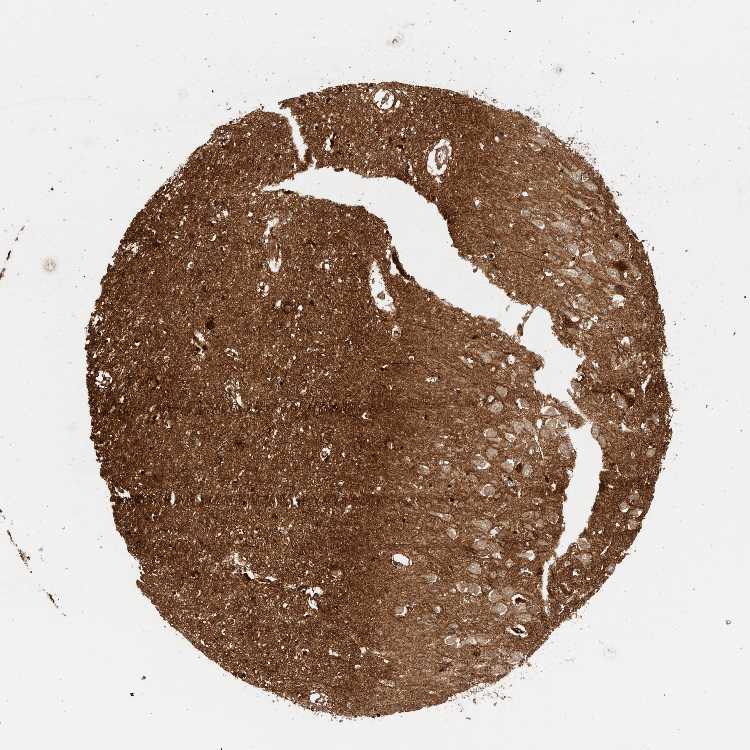

HIPPOCAMPUS - Antibody stainingi

Antibody staining in the annotated cell types in the current human tissue is reported as not detected, low, medium, or high, based on conventional immunohistochemistry profiling in selected tissues. This score is based on the combination of the staining intensity and fraction of stained cells.

Each image is clickable and will lead to virtual microscopy that enables deeper exploration of all samples and also displays staining intensity scores, fraction scores and subcellular localization as well as patient and tissue information for each sample.

Antibody HPA007865Antibody CAB025862

Glial cells Not detectedMedium

Neuronal cells LowLow

HIPPOCAMPAL FORMATION - Mouse brain profilei

Protein expression in mouse brain using immunofluorescence is reported as fluorescence intensity .

, antibody HPA007865

Hippocampal formation mean intensity 92.657